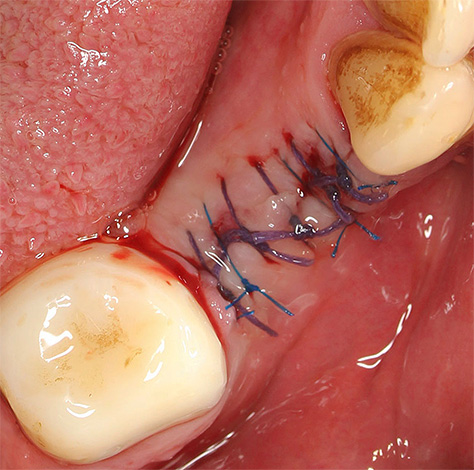

Se isso revelar o resultado de uma intervenção grosseira do dentista anterior (gengiva, bochecha, bordas afiadas dos alvéolos e ossos da mandíbula), o dentista-cirurgião pode retirar tecidos muito danificados que interferem na cicatrização, às vezes suaviza as bordas afiadas do osso ou morde as áreas salientes com pinças ósseas especiais. Depois disso, as suturas são quase sempre aplicadas e o paciente prende um cotonete estéril por 15 a 20 minutos para evitar sangramentos prolongados.

Após essa intervenção cirúrgica adicional, a temperatura pode voltar a elevar-se a valores altos, no entanto, este será um pagamento muito insignificante por se livrar de consequências muito mais graves que podem ameaçar sem assistência médica.